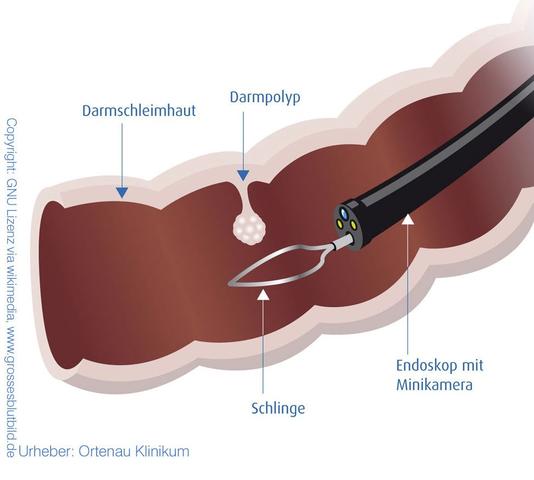

– Für die Untersuchungsdauer ca. eine halbe bis 1 Stunde einplanen, durch Polypenabtragungen oder technisch schwierige Untersuchungen kann jedoch mehr Zeit nötig sein.

– Die Untersuchung dauert in der Regel etwa eine halbe bis 1 Stunde, es kann jedoch länger dauern, wenn beispielsweise Polypen entfernt werden müssen.